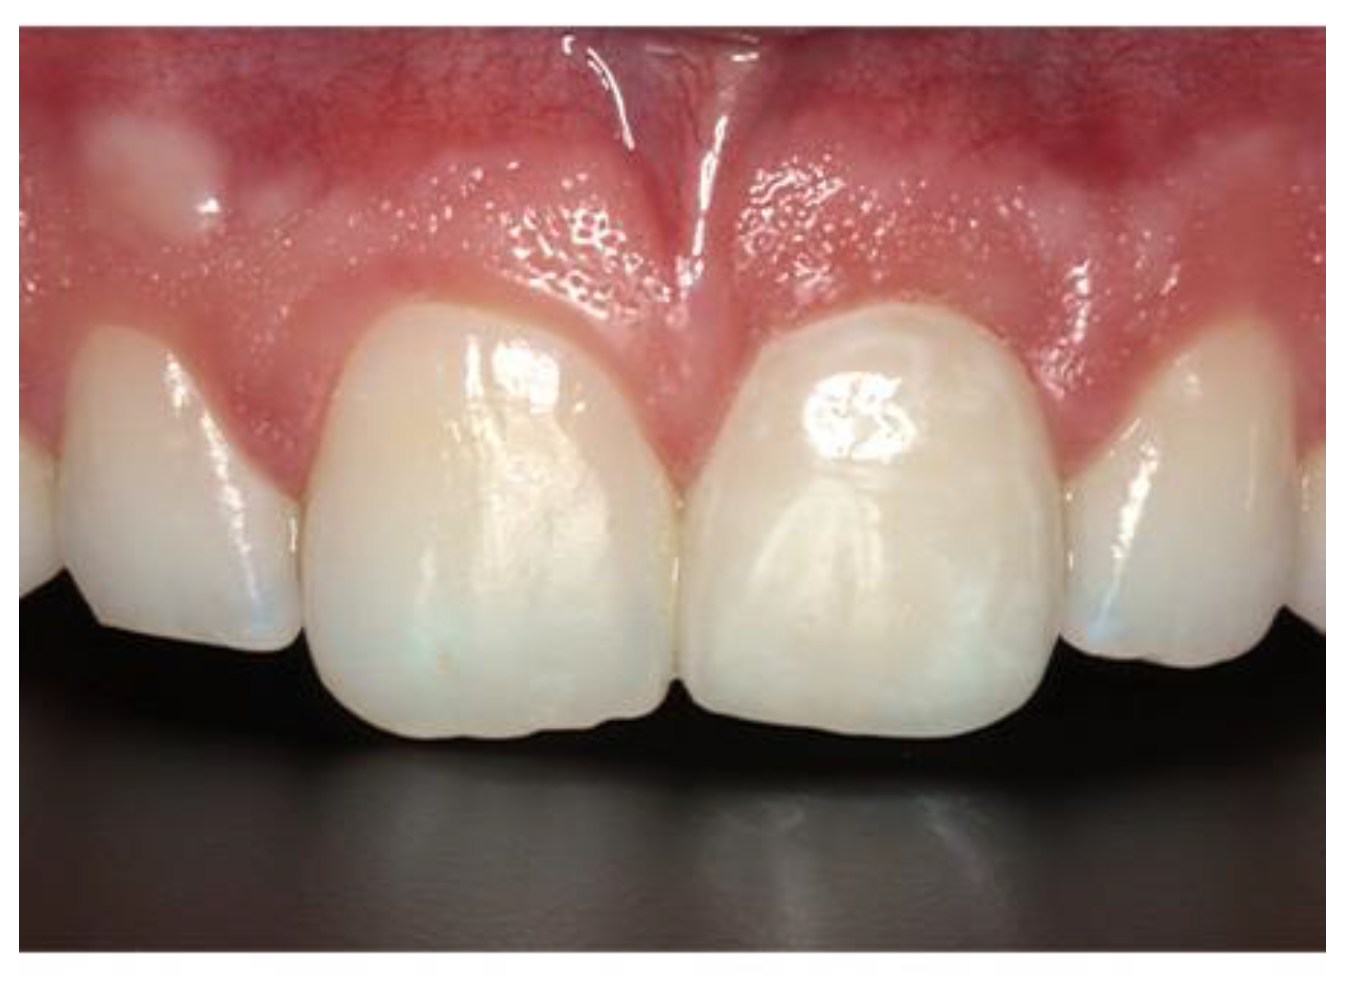

Figure 9. Postoperative image used for PES evaluation.

Preprints 86078 g008

Figure 16. Definitive restoration.

Preprints 86078 g013

Figure 19. Post-op ridge volume of definitive crown.

Preprints 86078 g016

Figure 20. Post-op labial view.

Preprints 86078 g017